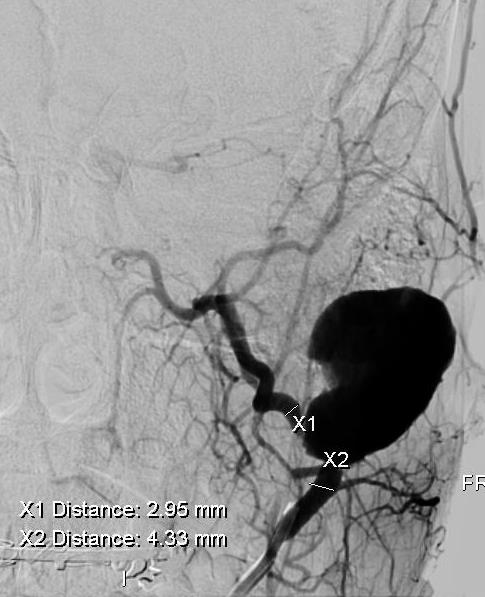

W dalszym etapie z nakłucia tętnicy udowej mikrocewnikiem przez tętnicę szyjną zewnętrzną dotarto do tętnicy szczękowej. Następnie za pomocą tytanowej sprężyny zamknięto odcinek dystalny tętnicy szczękowej (ryc. 3).

Ryc. 3. Angiogram prezentujący tętniak rzekomy oraz naczynia zaopatrujące.